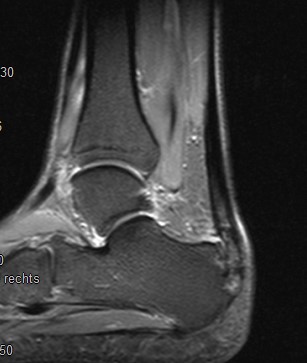

Abb. 2: Teilruptur Plantaraponeurose in der MRT Diagnostik

Eine Teilruptur der Plantaraponeurose kann ursprungsnah oder auch einige cm distal des Ursprungs als Folge einer direkten Gewalteinwirkung auftreten.

Zum Lesen der Bildbeschreibung und zur Vollansicht bitte das Bild anklicken. Bild: Manfred Thomas

In seltenen Fällen findet sich eine komplette Ruptur der Plantaraponeurose als Ursache der Beschwerden (siehe Abb. 3).